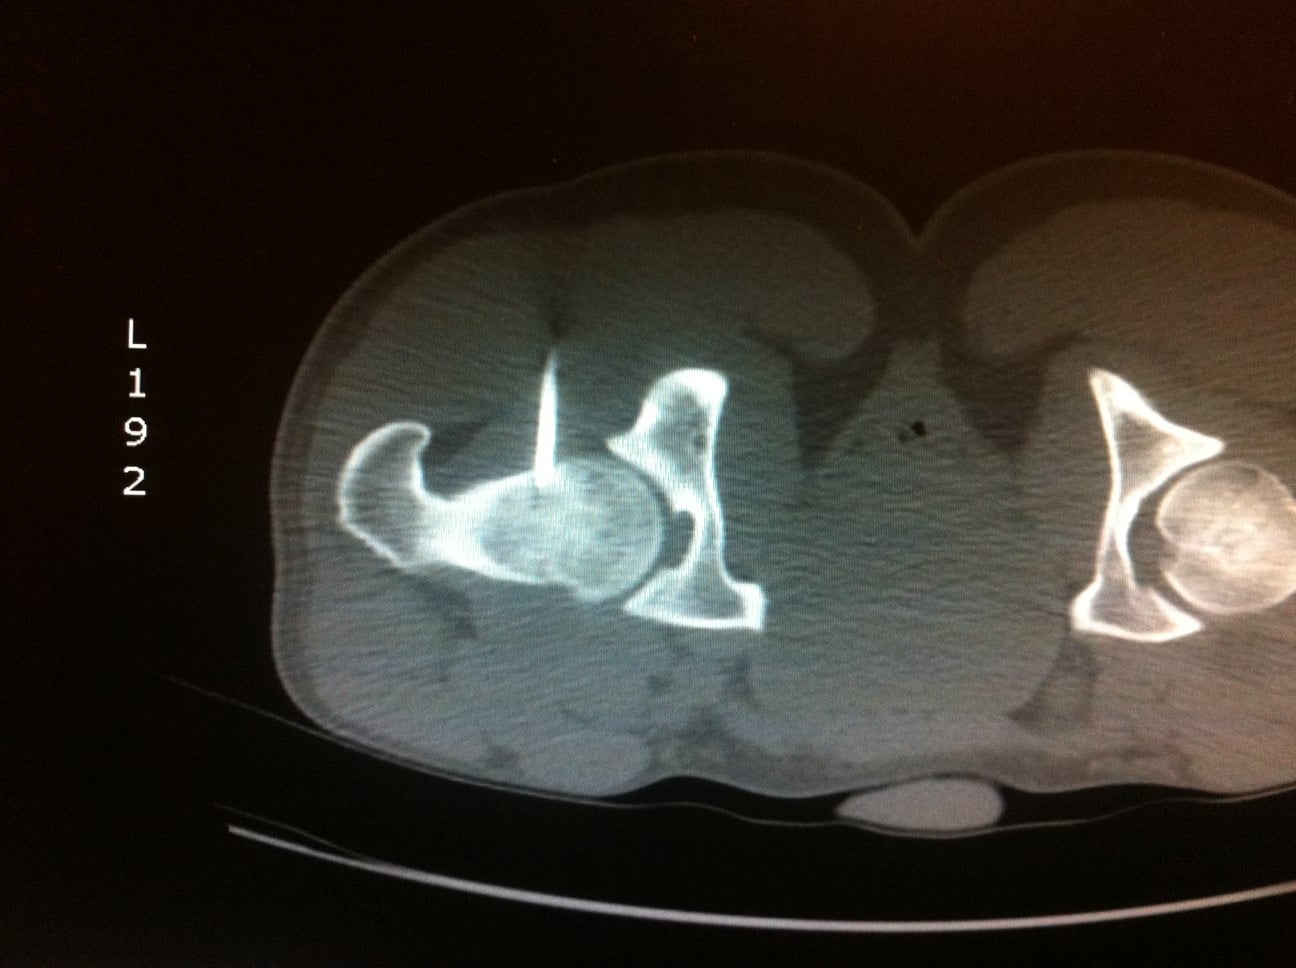

L’Examen est centré sur la région d’intérêt par Acquisition hélicoïdale de Coupes de 1 à 2mm jointives

Le scanner permet de repérer :

Le Nidus = hypodensité à contours nets associé à une hyperdensité calcique linéaire centro-tumorale correspondant à la vascularisation centrale. Une zone hypodense osseuse linéaire au niveau perilésionnel en regard de la condensation est assez spécifique. L’Ostéocondensation périphérique est homogène et peut provoquer une réaction périoste.